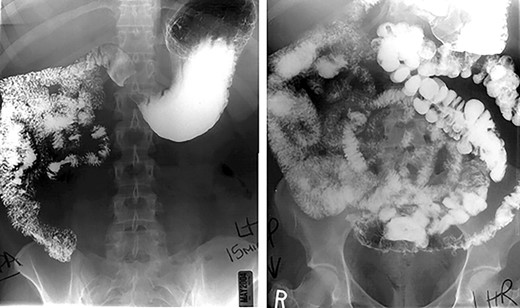

Preoperative work up in two patients (40%) included an upper gastrointestinal series (Fig. 1) revealing midgut non-rotation. The remaining (60%) patients in the series did not endorse gastrointestinal symptoms necessitating an upper gastrointestinal series, IM was identified intraoperatively. In the absence of preoperative diagnosis, malrotation was discovered intraoperatively when the entire greater omentum was found to the left of midline. Confirmation of the diagnosis was based on finding the entire small intestine to the right of midline, the cecum and ascending colon at midline or to the left of midline and the absence of a ligament of Treitz.

The operative course went as follows for those patients with IM discovered preoperatively: first, primary access to the peritoneal cavity was established with a 12 mm optical trocar placed approximately 4 cm to the left of the midline, 15 cm inferior to the xyphoid process. Second, a 5 mm port was placed in the epigastrium for liver retraction. Third, remaining ports (Fig. 2b) were slightly shifted to the right of our standard positions by 3–4 cm: 5 and 12 mm ports were placed in the right upper quadrant for the surgeon to complete the supramesocolic portion of the procedure. Fourth, 5 and 12 mm ports were placed in the left upper quadrant for the surgeon to complete the inframesocolic portion of the procedure. The first assistant used the ports opposite to the surgeon. Fifth, using these port positions, the surgeon can typically complete the upper abdominal portion of the operation from the patient’s right side and the lower abdominal portion of the operation from the patient’s left side. On the occasion that the orientation of the gastrojejunostomy does not provide adequate access for stapler placement or suturing from the patient’s right side, the surgeon can complete the anastomosis from the patient’s left. Sixth, a 15 ml gastric pouch was completed from the patient’s right side. Inspection of the lower abdomen confirmed the diagnosis of midgut non-rotation. The pylorus was identified and multiple Ladd’s bands were encountered. The entire small intestine was found in the right abdomen. With no rotation, the cecum is typically found in the midline of the lower abdomen and the majority of the remaining colon was often obscured by omentum. Seventh, the jejunojejunostomy was constructed using a ‘mirror image’ approach with the surgeon working from the patient’s left side. Our approach was to add 20 cm to our standard biliopancreatic limb length to account for mobility of the proximal small intestine related to the absence of the ligament of Treitz. Following division of Ladd’s bands, the pylorus is identified, and the jejunum transected 80 cm distal. A 100 cm Roux limb is right-oriented with a right-sided biliopancreatic limb and an antiperistaltic jejunojejunostomy. The anastomosis was constructed using a linear-stapler technique with sutured enterostomy closure; the mesenteric defect was closed with a running non-absorbable suture. The Roux limb was passed in an antegastric, paracolic fashion to allow construction of the gastrojejunostomy. The anastomosis was completed using the same technique as the jejunonejunostomy (Fig. 3). This was completed from the left side of the patient.